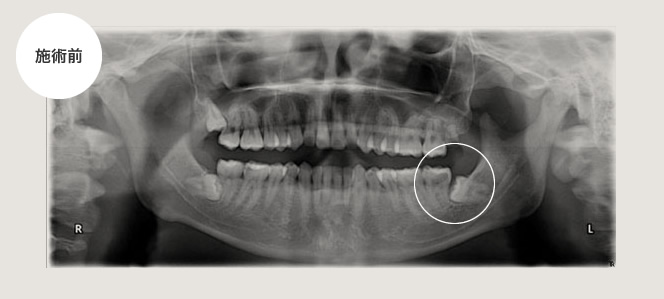

手前の歯が虫歯になってしまった例、及び抜く必要がない場合

左下がズキズキ痛むという主訴で来院されました。

原因は親知らずの一つ手前の歯が歯髄炎になってしまっていたので、神経の処置を通法通り行いましたが、親知らずの頭が一部でていたため、そこに汚れがたまり手前の歯が虫歯になってしまったため左下は抜歯しました。

右下は完全に骨の中に埋まっている状態でしたので抜く必要はありません。